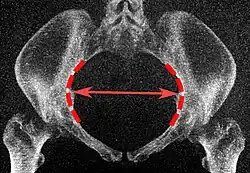

| Abertura superior da pelve | Diâmetro transverso da abertura superior |

![]() Plano coronal |

As linhas iliopectíneas, na maior distância transversa. | 13 a 14,5 cm.[4] |